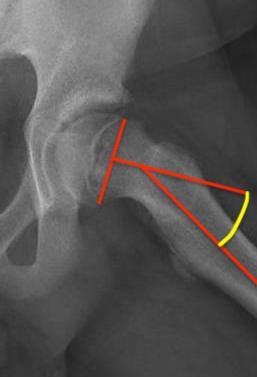

Southwick classification

Southwick Angle / Slip Angle

- epiphyseal-diaphyseal angle on frog leg lateral

- mild <30°

- moderate 30- 50°

- severe >50°

Mild Moderate Severe